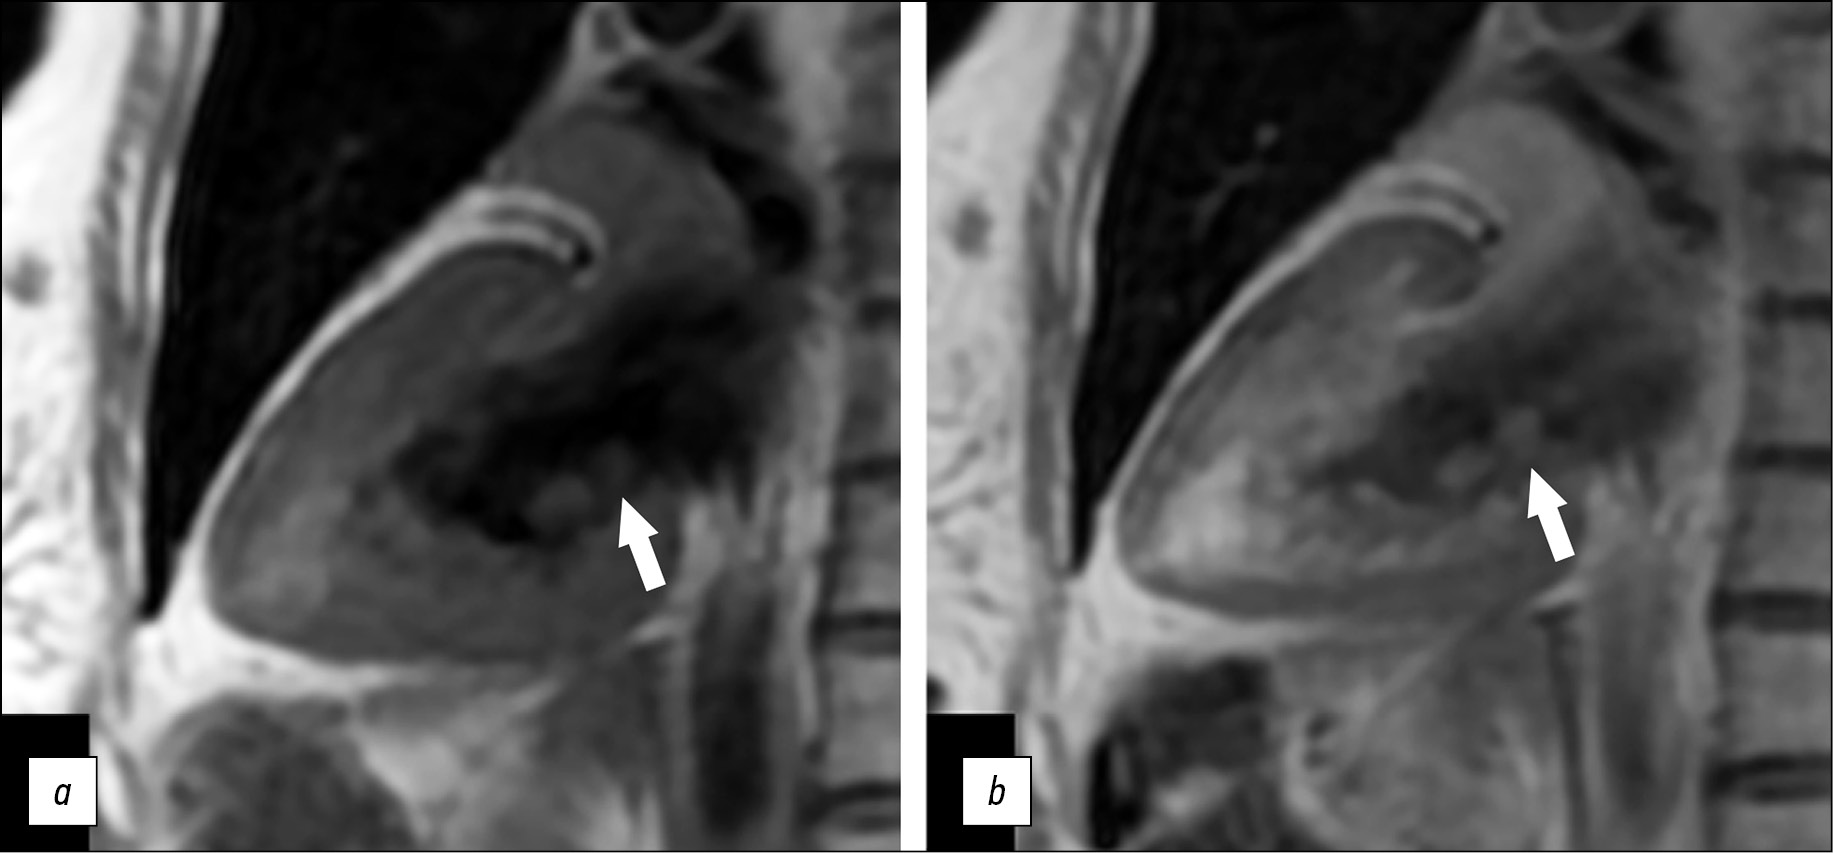

A small round-shaped mass (5 × 8 mm in size) on the posterior mitral valve leaflet on the left atrial side was confirmed. The examination was performed before and after early and delayed contrast enhancement using T2 SS, FSE, and FS pulse sequences—T2 WI with signal suppression from blood and adipose tissue—and PS MDE (PSIR), TI 250 ms postcontrast images to obtain tissue mass characteristics. A contrast agent (gadopentetic acid) was injected at 0.2 ml/ kg body weight.

After delayed contrast enhancement, an increased signal was observed compared to the native T1-WI series (Fig. 3).

Fig. 3. Magnetic resonance imaging of the heart, two-chamber view: a, native T1-WI series, TSE; b, postcontrast T1-WI series, TSE. Additional mass on the posterior mitral valve leaflet (white arrows).